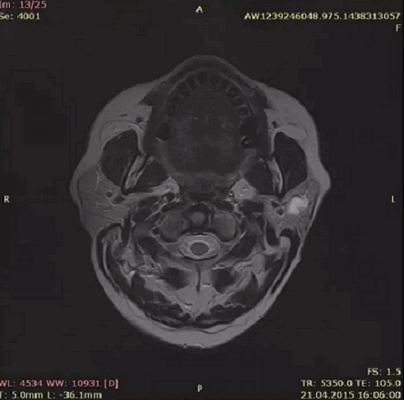

КТ, МРТ при добавочной слюнной железе в поднижнечелюстном пространстве

Для выявления болезней слюнных желез (сиалоаденит, синдром Шегрена, закупорка протоков камнями) применяются лучевые методы - КТ, МРТ, УЗИ. Специфичность компьютерной томографии при нозологических формах около 100%, достоверность - 98%. Показатели высокие для достоверной верификации патологии околоушных, подчелюстных желез. Ограничивает повсеместное применение метода радиационное облучение. Разовая обследование не приносит вреда, но не рекомендуется делать сканирование часто (за исключением верификации новообразований).

КТ-сиалография применяется при остром и хроническом течении слюннокаменной болезни, сиалоаденита, паротита, паротите Шегрена. Способ позволяет правильно поставить диагноз, выявить локализацию, распространенность, стадию патологического процесса.

КТ-признаки слюннокаменной болезни

Отечность, увеличение околоушной и поднижнечелюстной областей, не проходящие после приема фармацевтических препаратов - показание к лучевой диагностике. Симптомы обуславливает не только сиалоаденит. Слюннокаменная закупорка (сиалолитиаз) определяется после КТ-сиалографии по следующим признакам:

- Увеличение размеров поврежденного органа;

- Сохранение однородности структуры;

- Расширение протока.